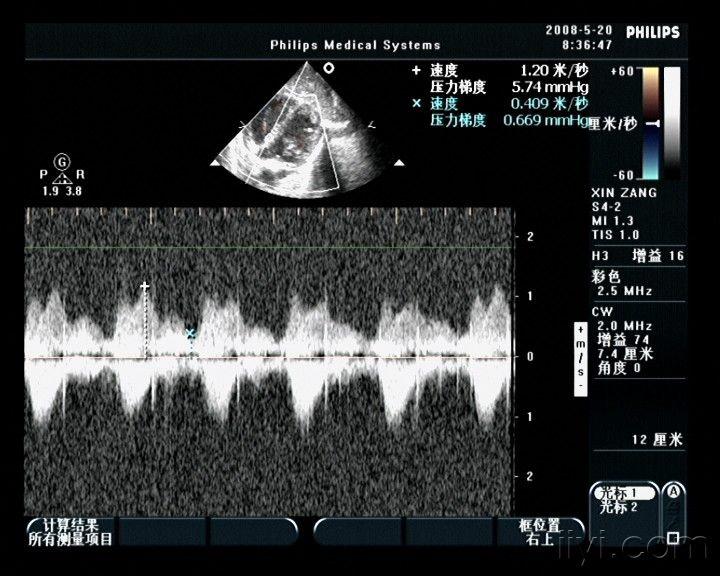

口,短箭头所示隔膜la : 真房, lv :左室,aa :副房图 1 心尖五腔心切面

心尖五腔切面分流频谱图